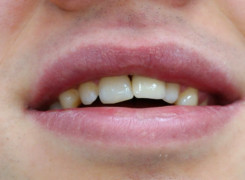

Pan Ryszard trafił do Naszego Gabinetu z jasno sprecyzowanym oczekiwaniem. Miał 84 lata i chciał odzyskać możliwość swobodnego spożywania posiłków oraz poprawienia sobie komfortu życia a także prosił aby przywrócić mu piękny uśmiech jakim cieszył się przed laty. Już na początku pierwszej rozmowy zastrzegł, że interesuje go wyłączenie rozwiązanie uzupełnieniem protetycznym stałym. Nie miał zamiaru użytkować żadnych protez ruchomych. Mając na uwadze powyższe wykonaliśmy Panu Ryszardowi zdjęcie pantomograficzne oraz badanie tomograficzne szczęki i żuchwy na postawie których zapanowywaliśmy Pacjentowi optymalne rozwiązanie – stałe uzupełnienie protetyczne w postaci 28 koron cyrkonowych zamontowanych do dwóch belek cyrkonowych które będą przymocowane do 16 implantów w konfiguracji 8 wszczepów w szczęcie 8 w żuchwie. Po omówieniu powyższego planu przystąpiliśmy do Wspólnej pracy której efekty w poszczególnych etapach prezentujemy poniżej.